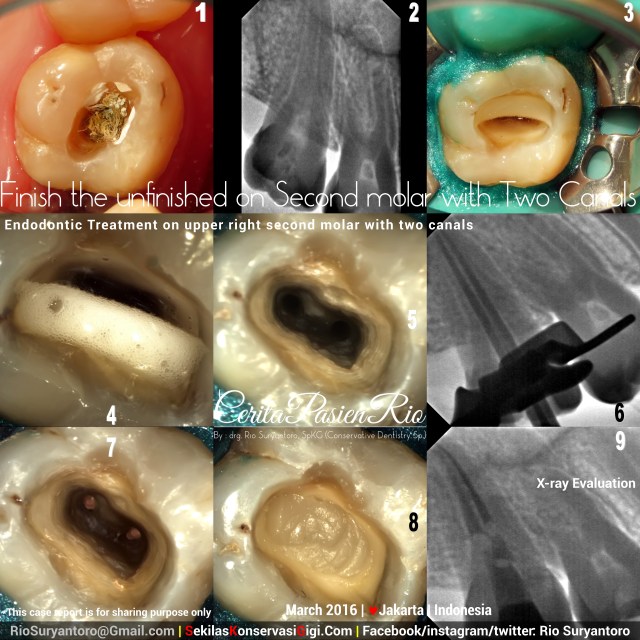

So.. i got a patient who had her tooth already treated by another operator but it is not yet finished although this patient already asked the operator regarding the goals of this dental treatment.…

After taking proper consent, i started my endodontic treatment for her.

Cleaning and shaping was done with Protaper_Next (Dentsply), coronally sealed with low_shrinkage stress flowable composite Filtek_Bulkfil (3M) up to orifices, and continued with Z250 XT (3M) up to 2 mm below occlusal level.. xray image evaluated with durr sensor at 60kV, 3mA, 0,03 second. Next visit will be an occlusal top restoration with composite resin.